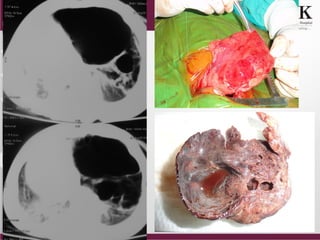

A new born with

respiratory distress

Cystic adenomatoid malformation

Air filled cystic spaces:

Congenital Cystic Adenomatoid Malformation

CONGENITAL LOBAR EMPHYSEMA

CDH CCAM Pneumatocoel

pneumothorax

CLE CLE